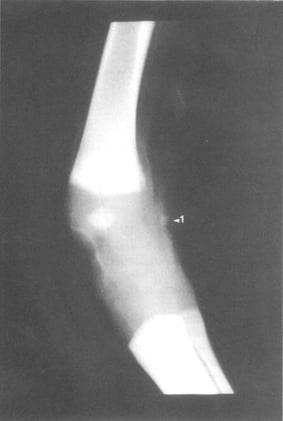

- Anatomy

Anatomy